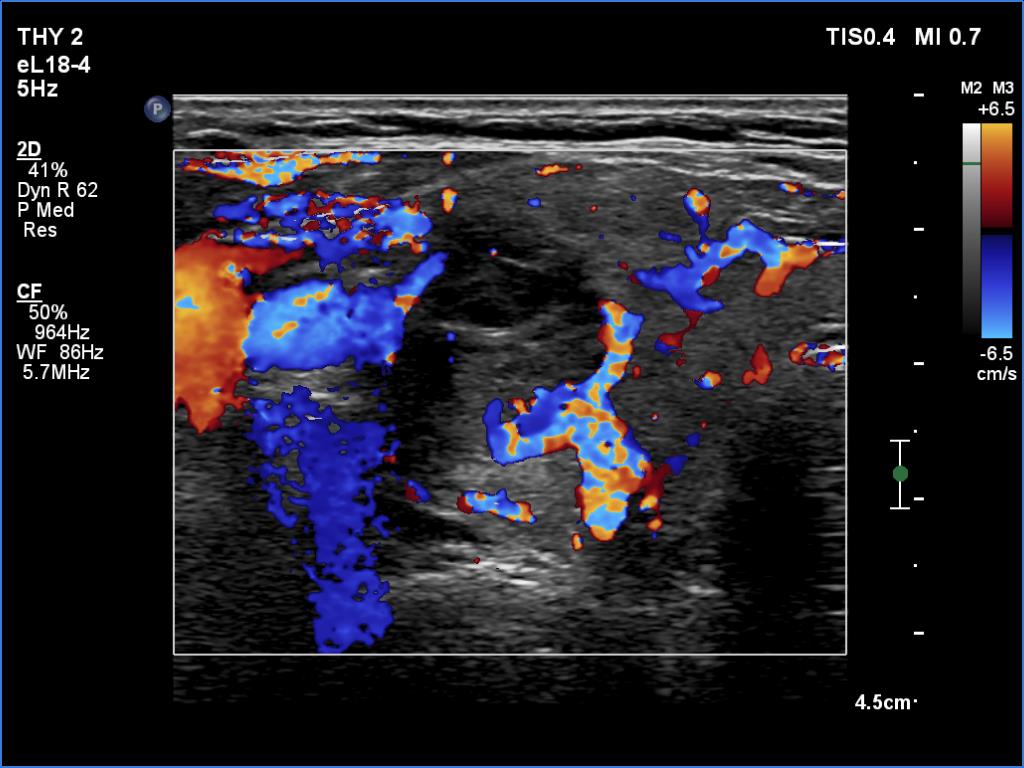

One year after the first examination (second row of images):

Clinical presentation. The patient had no complaints She came to follow-up visit.

Palpation: unchanged.

Results of blood tests: subclinical hyperthyroidism on daily 10 mg methimazole (TSH 0.001 mIU/L, FT4 13.8 pM/L, TSAb 8.2 U/L (normal value below 1.5)).

Ultrasonography. The thyroid became more hypoechoic while the lesion in the central part of the right lobe did hyperechoic. The vascularization of the thyroid was extremely increased.The patient was told that it is very likely that her hyperthyroidism will relapse therefore we suggested radioiodine therapy.